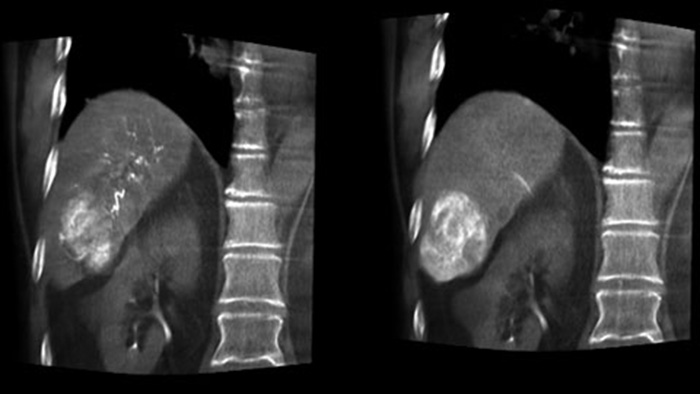

A post embolisation 3D acquisition allows you to visualise the targeted deposition of embolic material, such as Liopidol or radiopaque beads, in the tumor.5

Dual View allows simultaneous visualisation of pre-embolisation arterial phase 3D image and the post embolisation image to assess treatment endpoint.